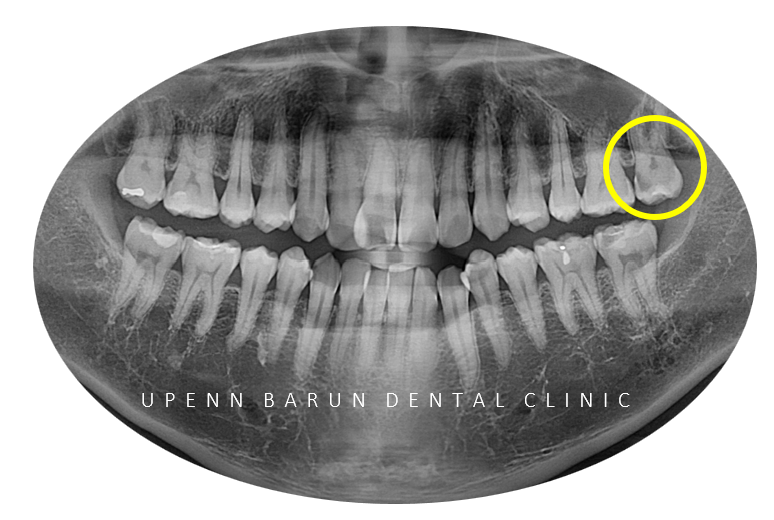

환자분께서는

부정교합3급 환자분으로

반대교합이 있으셨습니다.

비발치교정을 원하셨던 이 환자분은

치아 크기에 비해 악궁이 현저히 좁아

악궁확장장치가 필요하신 상황이었습니다. T^T

교정을 시작하기 앞서

같은 원장님께 교정, 충치치료까지 가능한

유펜바른치과에서

충치치료를 마무리 해드리고

교정을 진행해드렸습니다 :)